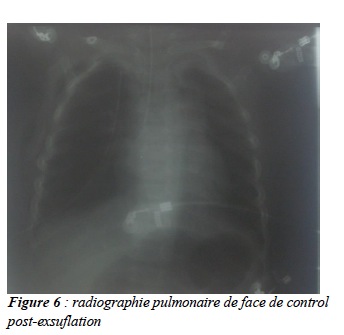

En absence de bronchoscope pédiatrique dans les services, l’enfant a été transféré en chirurgie thoracique. Il a bénéficié d’une thoracotomie avec extraction du corps étranger (fig 4 et 5) et d’un drainage du pneumothorax. L’évolution a été favorable. (Fig : 6).